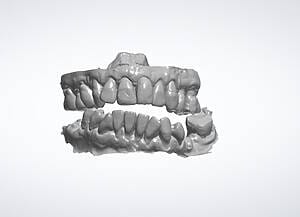

Natalie’s treatment began with a comprehensive clinical assessment, including a review of her medical and dental history, a full examination, and analysis of her functional difficulties such as her tongue habit and altered bite. A 3D cone-beam CT scan was then taken to assess bone quality and volume, identify areas of infection, and map important anatomical structures to ensure safe implant placement.

Alongside this, a digital intraoral scan and detailed photographic records were captured. These provided accurate models of her teeth and bite, as well as valuable information about facial proportions and smile aesthetics. Together, these records ensured that planning would address both the functional and cosmetic aspects of her rehabilitation.

All data were transferred into digital treatment planning software, allowing virtual placement of implants and collaboration with the dental laboratory before surgery. This enabled careful evaluation of long-term outcomes and ensured the design of provisional and final prosthetics could be completed with precision. Following these discussions, the decision was made to proceed with the Fixed-Teeth-in-a-Day approach using the All-on-4 technique.